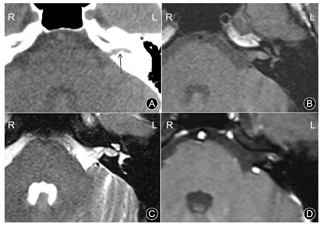

影像学检查:CT平扫示左侧IAC后壁下钙化灶隆起,致IAC狭窄。MRI成像示病灶最大径约6 mm,未累及桥小脑角区。TSE序列的T1WI扫描上病灶呈略高信号,脂肪抑制TSE序列的T2WI上呈稍高信号。弥散加权图像上病灶未见扩散受限表现。注射钆喷葡胺造影剂行横断面T1WI增强扫描,病灶边缘见斑点状明显强化影(图3),延迟后冠状面T1WI增强扫描强化范围未见明显变化。

例2:术后1周,恢复可,伤口无明显红肿渗出,无发热,无耳鸣、眩晕,无面瘫,抬头看高时稍有复视。术后6个月复查耳部MRI平扫+增强示,内听道未见异常强化软组织灶占位(图4)。门诊随访4年,无复发。

关于IAC血管瘤的影像特征方面,Zhu等[3]曾对6例IAC海绵状血管瘤的CT进行研究,发现病灶在CT上主要表现为IAC的增宽伴病灶区的钙化灶。本组2例IAC-VH在CT上均发现了位于IAC后壁下的不规则钙化灶,甚至当钙化灶较大时可致IAC局部狭窄,这种特征性表现亦在手术中得到了证实。而这种钙化灶却在IAC听神经鞘瘤中很少见到。MRI检查示,2例IAC-VH在T1WI上均呈稍高信号,脂肪抑制T2WI上呈稍高信号,且病灶内未见明显的囊变坏死,与Pappas DG等[9]既往观察IAC海绵状血管瘤的MRI平扫特征类似。DWI上,病灶内未见扩散受限表现。注射造影剂后行增强扫描显示,2例病灶的边缘均见斑点状的显著强化影,而病灶内部未见明显强化。该征象作为IAC-VH特征性的强化表现,在IAC神经鞘瘤中很少见,故2例病灶术前MRI诊断中均被考虑为IAC血管瘤的可能性更大。延迟3分钟后行冠状面增强示,病灶的强化范围与横断面相仿,未见类似于海绵状血管瘤样的典型"向心性填充样强化"改变,以此可同IAC海绵状血管瘤相鉴别。